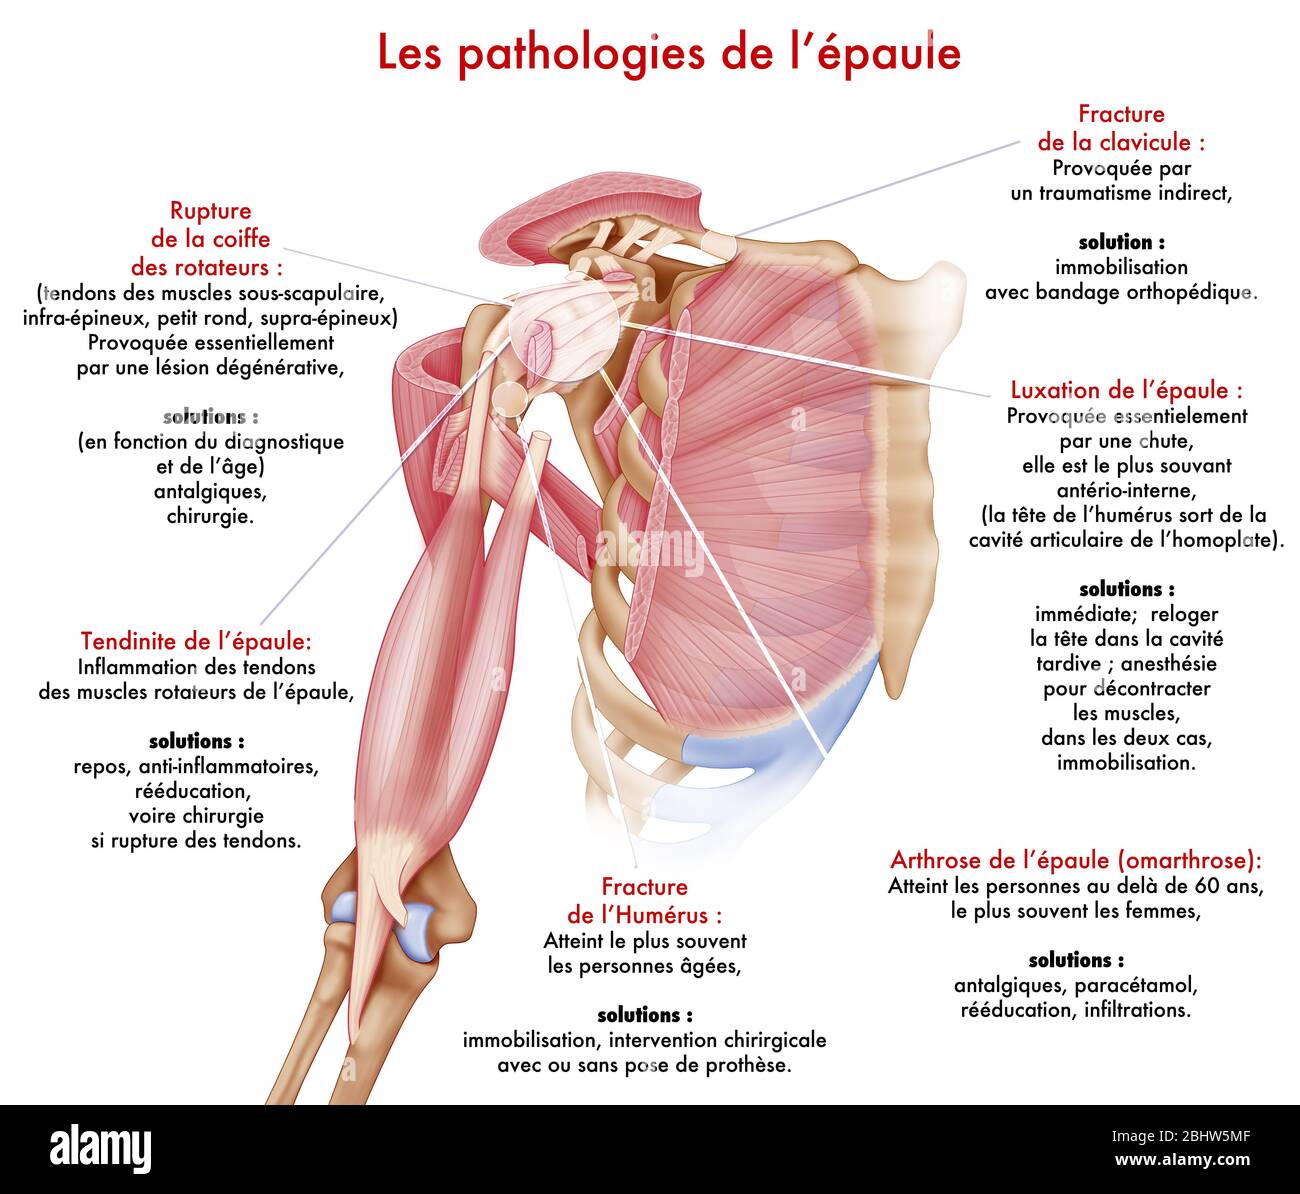

Medical illustration representing pathologies of the shoulder. The articular capsule, the ligaments, the small pectoralis and coraco-brachial tendons Stock Photohttps://www.alamy.com/image-license-details/?v=1https://www.alamy.com/medical-illustration-representing-pathologies-of-the-shoulder-the-articular-capsule-the-ligaments-the-small-pectoralis-and-coraco-brachial-tendons-image355209807.html

Medical illustration representing pathologies of the shoulder. The articular capsule, the ligaments, the small pectoralis and coraco-brachial tendons Stock Photohttps://www.alamy.com/image-license-details/?v=1https://www.alamy.com/medical-illustration-representing-pathologies-of-the-shoulder-the-articular-capsule-the-ligaments-the-small-pectoralis-and-coraco-brachial-tendons-image355209807.htmlRM2BHW5MF–Medical illustration representing pathologies of the shoulder. The articular capsule, the ligaments, the small pectoralis and coraco-brachial tendons

Medical illustration representing the muscles of the shoulder, joint and shoulder muscles. The articular capsule, the ligaments, the small pectoralis Stock Photohttps://www.alamy.com/image-license-details/?v=1https://www.alamy.com/medical-illustration-representing-the-muscles-of-the-shoulder-joint-and-shoulder-muscles-the-articular-capsule-the-ligaments-the-small-pectoralis-image355209794.html

Medical illustration representing the muscles of the shoulder, joint and shoulder muscles. The articular capsule, the ligaments, the small pectoralis Stock Photohttps://www.alamy.com/image-license-details/?v=1https://www.alamy.com/medical-illustration-representing-the-muscles-of-the-shoulder-joint-and-shoulder-muscles-the-articular-capsule-the-ligaments-the-small-pectoralis-image355209794.htmlRM2BHW5M2–Medical illustration representing the muscles of the shoulder, joint and shoulder muscles. The articular capsule, the ligaments, the small pectoralis